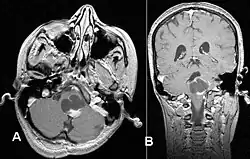

Pilocytic astrocytoma in the hypothalamic region

Axial non-contrast CT in a nine-year-old girl showing a slightly hypodense mass in the tectum of the brainstem, compressing the aqueduct of Sylvius and causing obstructive hydrocephalus

Sagittal T1-weighted MRI showing a well-circumscribed hypointense mass in the tectum (presumably a tectal plate glioma). These lesions are a distinct subset of pilocytic astrocytoma which present with hydrocephalus typically in 6 to 10 year-olds and are rarely progressive lesions. When imaging is characteristic, a biopsy is usually not performed because of the risks to adjacent structures, often shunting to relieve intracranial pressure is the only treatment required.

T1-weighted coronal MRI image postcontrast showing heterogeneous contrast enhancement within the presumed tectal plate glioma